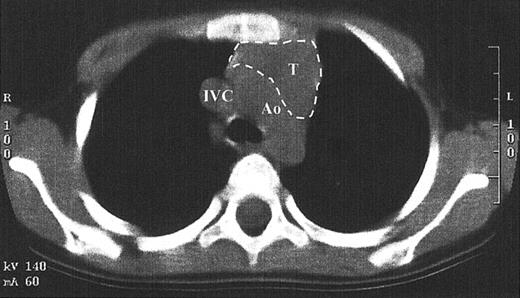

While TRECs are an excellent surrogate marker for thymic function, little direct data exist that show thymopoiesis. This is in part due to the inappropriateness of performing a thymic biopsy in children who have developed normal function. Since the pretransplantation SCID thymus is vestigial, weighing less than a gram, it is difficult to find by radiography.1,14 A computed tomography scan of the anterior mediastinum of the Jak3-deficient SCID patient at 4 years after transplantation shown in Figure 6demonstrates a thymus with a transverse dimension of 3.8 cm, which is normal for age.16 The thymus expansion seen here provides further evidence for thymopoiesis after hematopoietic stem cell transplantation in SCID.

Computed tomography scan of the anterior mediastinum of a Jak3-deficient SCID patient 4 years after transplantation.

Thymic tissue is indicated by the dashed lines. It is in the normal position and measures 3.8 cm in its greatest transverse dimension, which is normal for age. Ao indicates aortic arch; IVC, inferior vena cava; T, thymus.